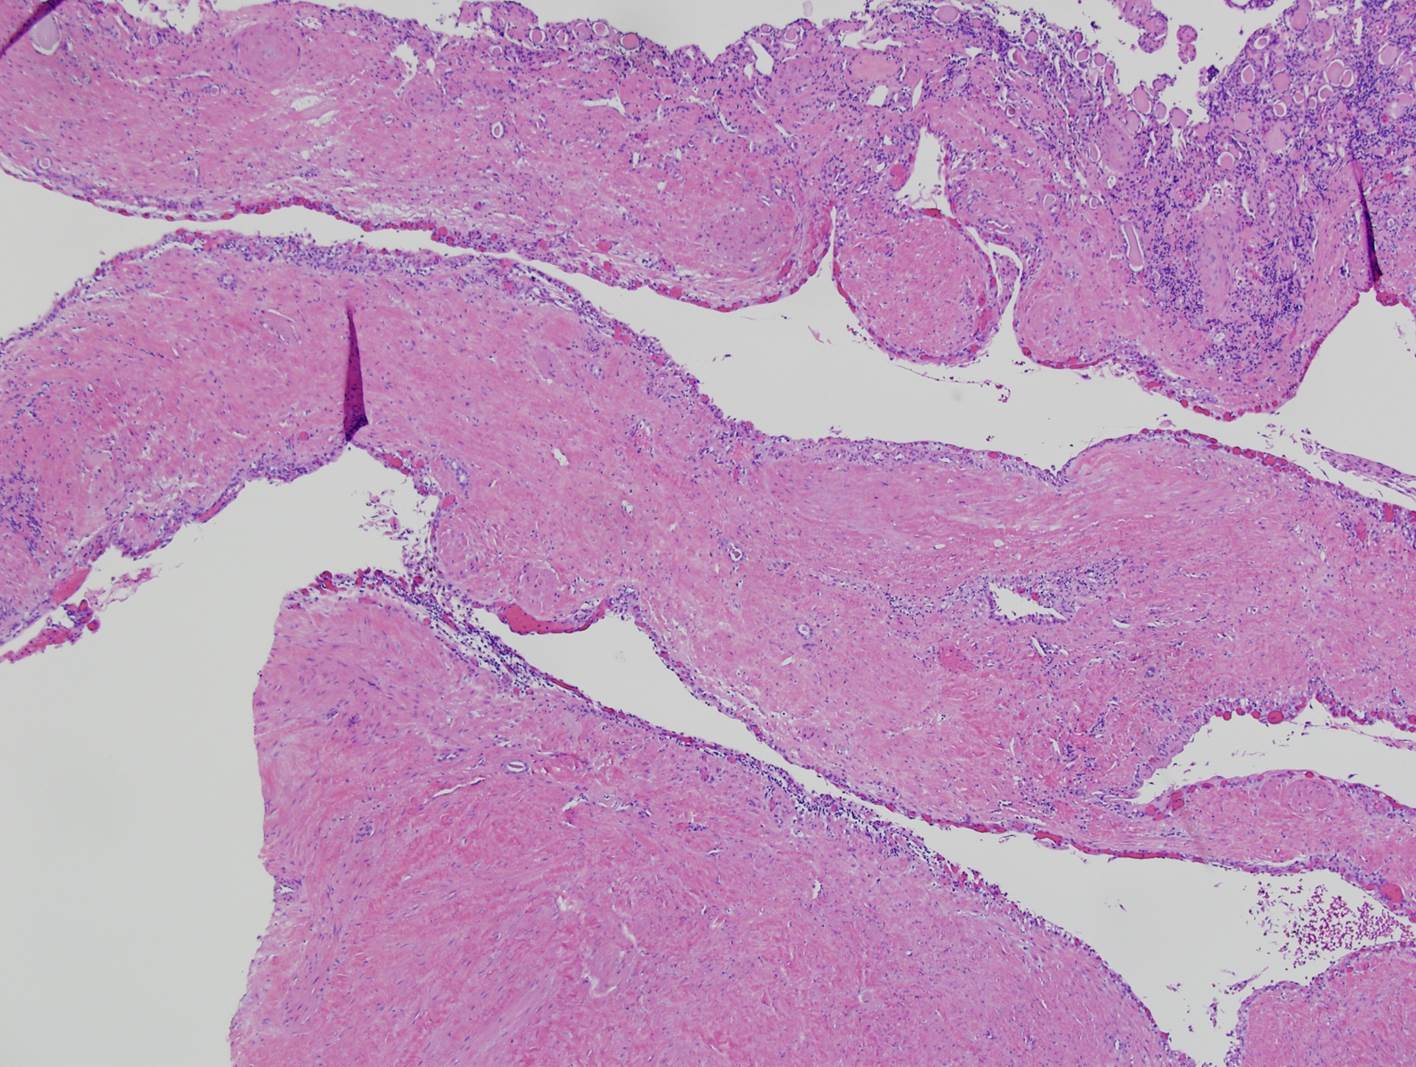

Classification of renal tumors

Case ID: 809